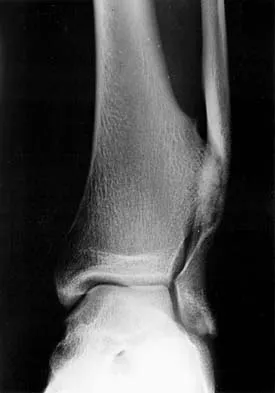

Figures 3a and 3b show the inversion stress radiographs of a patient's ankle. What is the most likely ligament injury pattern?